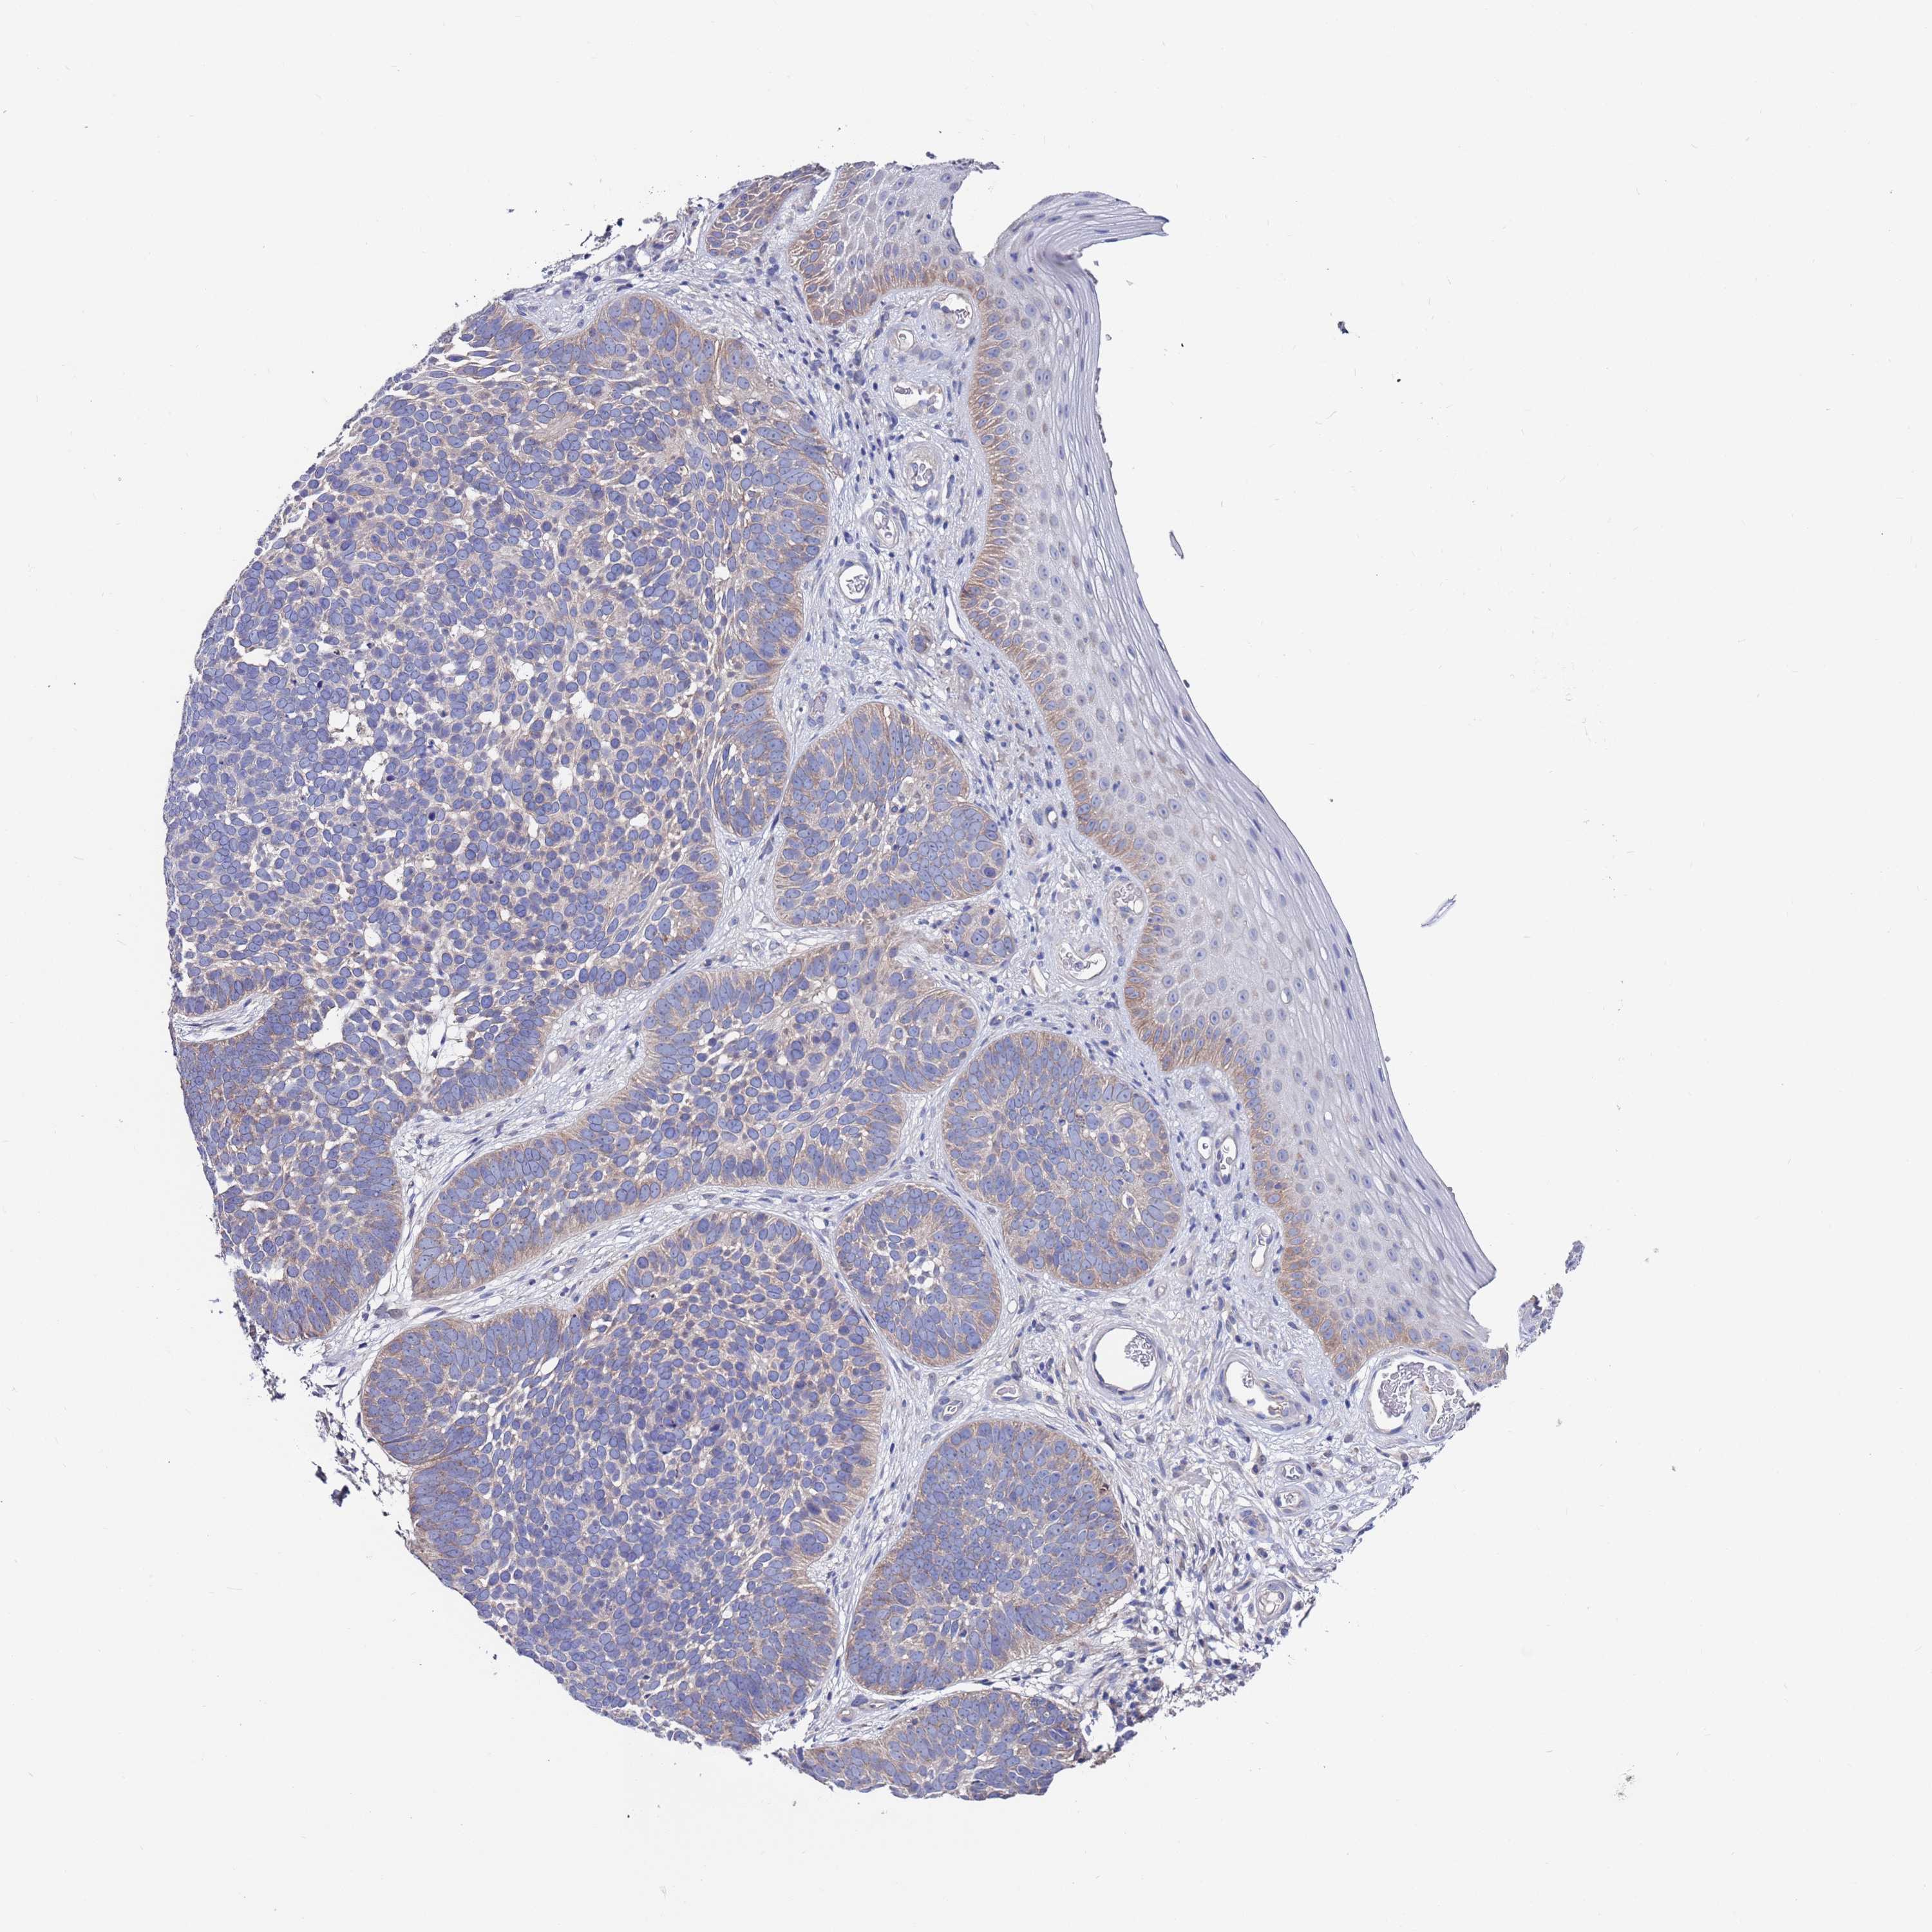

Basal cell and squamous cell cancer

SKIN CANCER - Protein expressioni

A mouse-over function shows sample information and annotation data. Click on an image to view it in a full screen mode. Samples can be filtered based on level of antibody staining by selecting one or several of the following categories: high, medium, low and not detected. The assay and annotation is described here.

Antibody stainingi

Antibody staining in the annotated cell types in the current human tissue is reported as not detected, low, medium, or high, based on conventional immunohistochemistry profiling in selected tissues. This score is based on the combination of the staining intensity and fraction of stained cells.

Each image is clickable and will lead to virtual microscopy that enables deeper exploration of all samples and also displays staining intensity scores, fraction scores and subcellular localization as well as patient and tissue information for each sample.

Antibody HPA047136

Staining

High

Medium

Low

Not detected

Intensity

Strong

Moderate

Weak

Negative

Quantity

>75%

75%-25%

<25%

None

Location

Nuclear

Cytoplasmic/membranous

Cytoplasmic/membranous,nuclear

Basal cell carcinoma